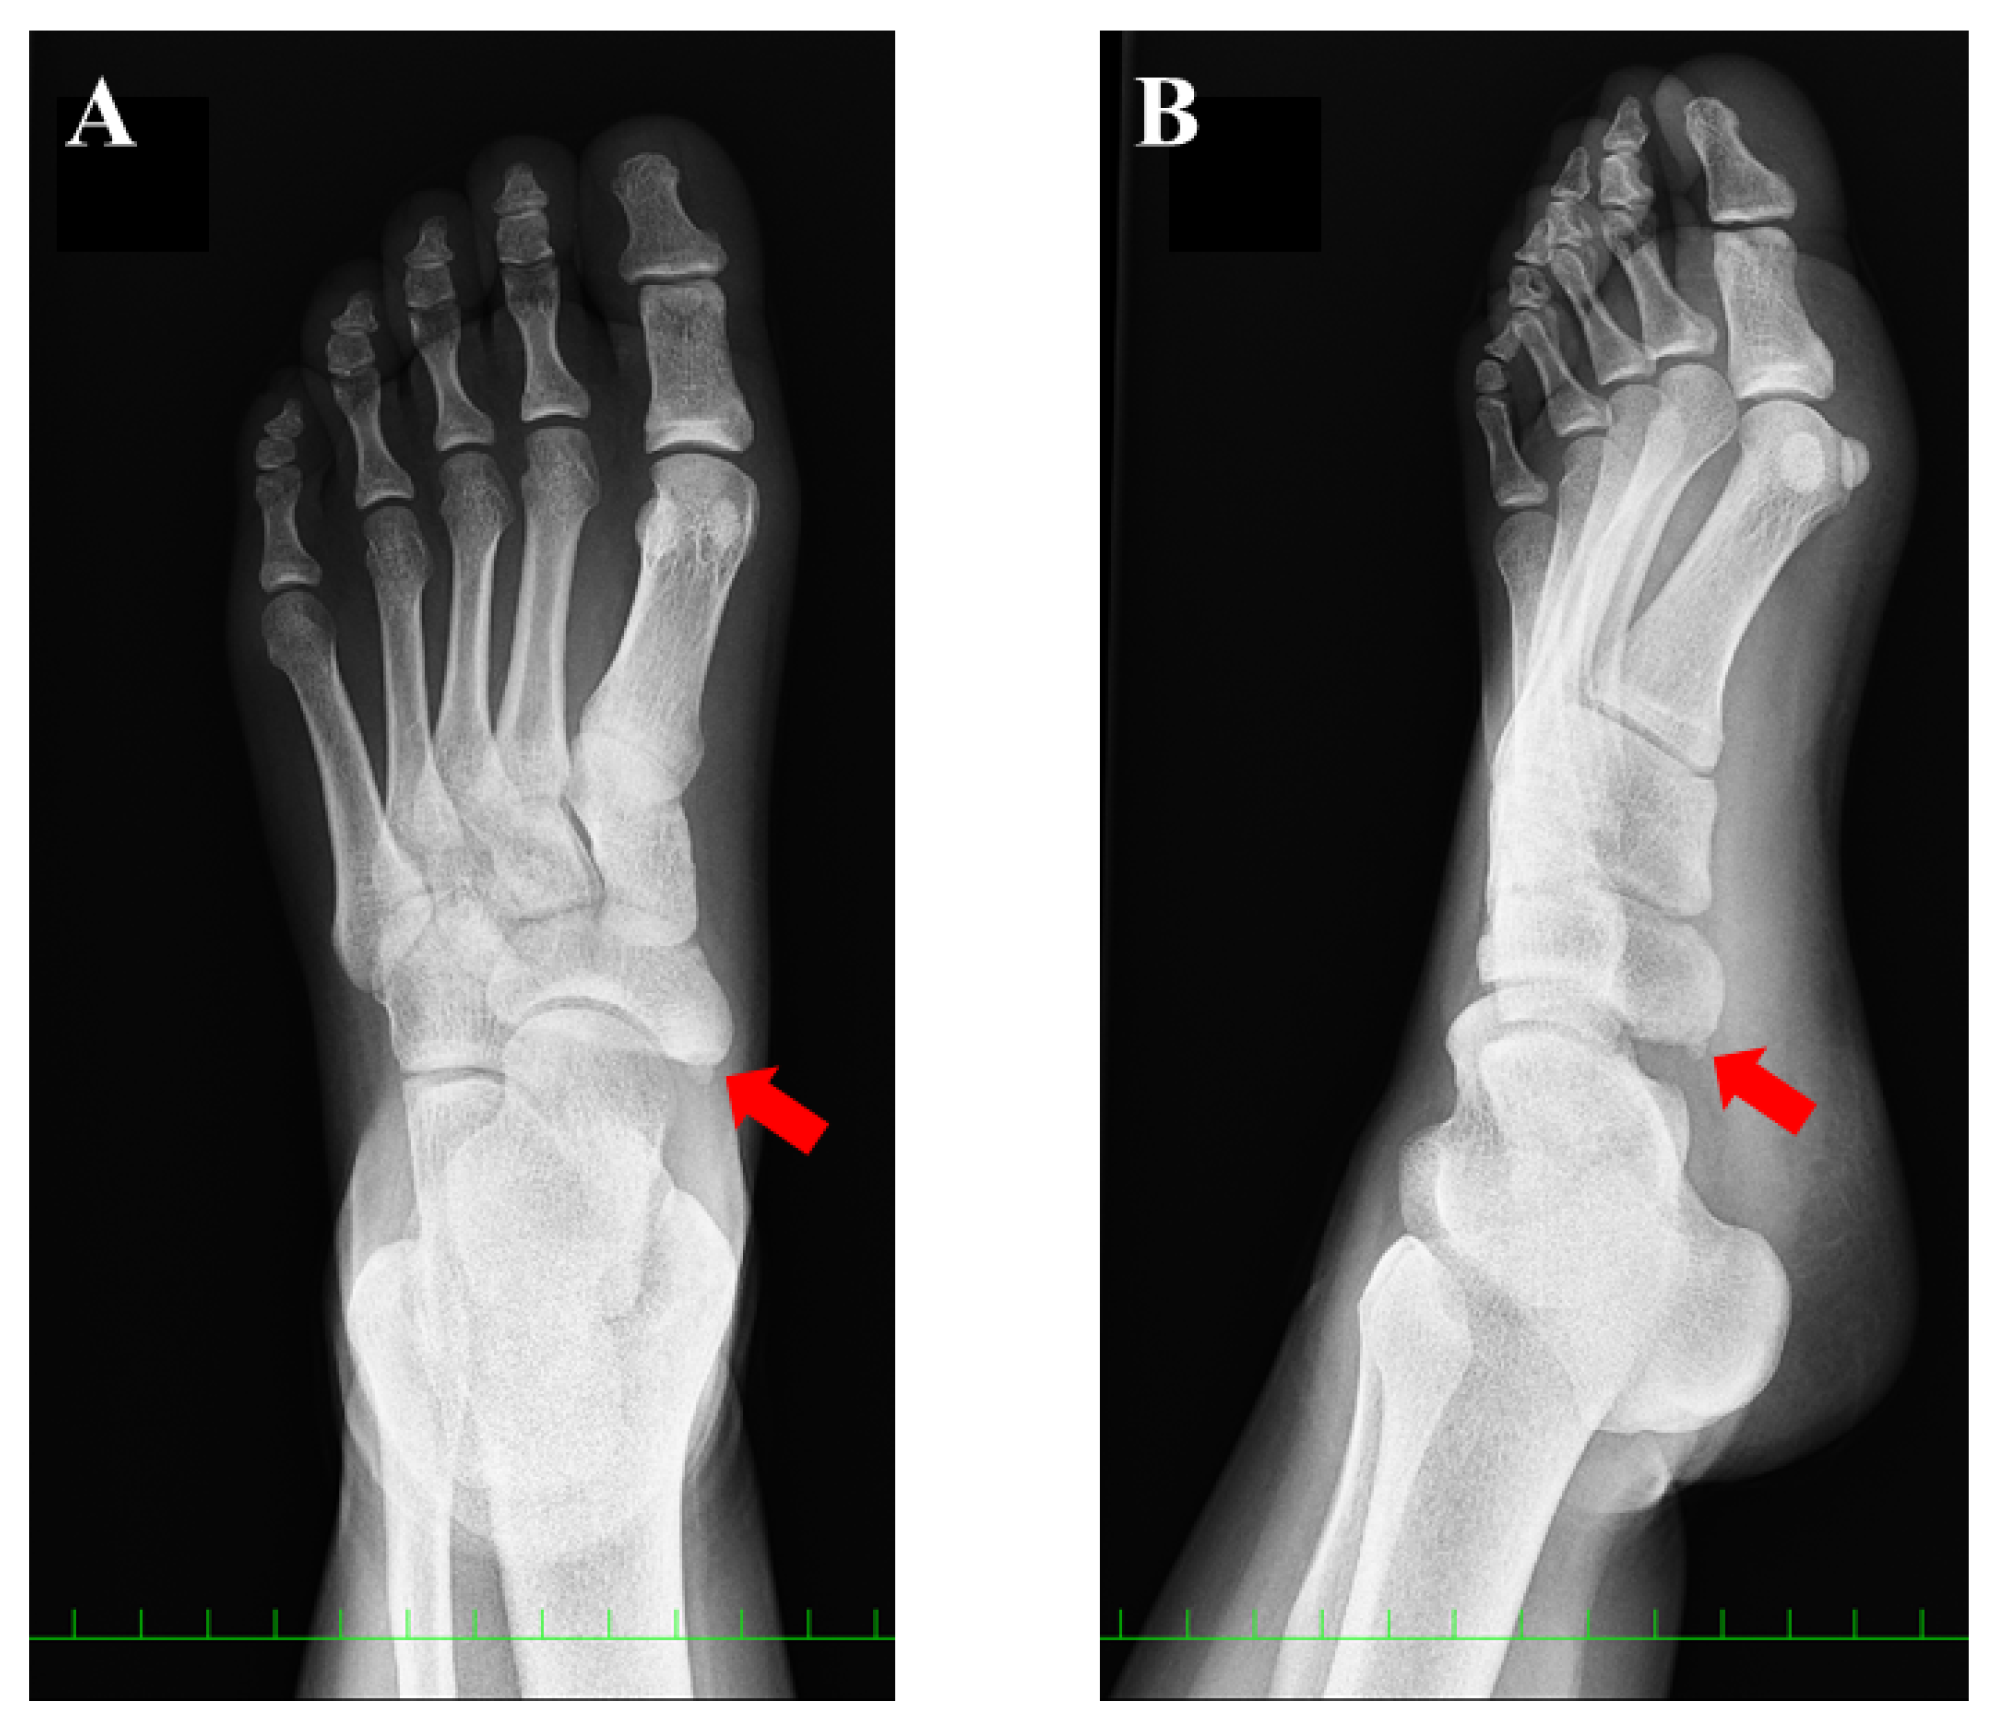

A 15-year-old girl was referred to our department for the assessment of left foot pain. She was diagnosed with AN, which was radiographically classified as Veitch type Ⅰ at a private orthopedic clinic (Figure 1).

Figure 1.

Preoperative plain radiographic findings: (A) anteroposterior view and (B) oblique view. The red arrow indicates the accessory navicular (AN). The AN was classified as type 1, according to the Veitch classification.